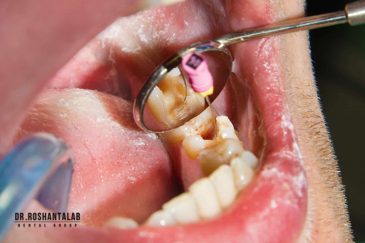

از عصب کشی و درمان ریشه دندان گرفته تا جراحی لثه و کشیدن دندان، تمامی مراحل توسط متخصص ترمیم دندان مدیریت میشود. ارائه باکیفیتترین خدمات ترمیم دندان برای سلامتی شماست.کاشت ایمپلنت فوری دندان